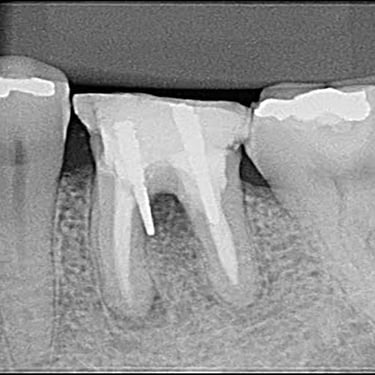

Calcificación Pulpar

La calcificación pulpar es la formación de depósitos de calcio dentro de la pulpa dental, que puede dificultar el tratamiento de conducto.

Los pacientes generalmente no tienen síntomas, pero pueden experimentar sensibilidad.

El tratamiento incluye la eliminación de los depósitos durante el tratamiento de conducto. Es importante tratarlo para evitar complicaciones durante el procedimiento.